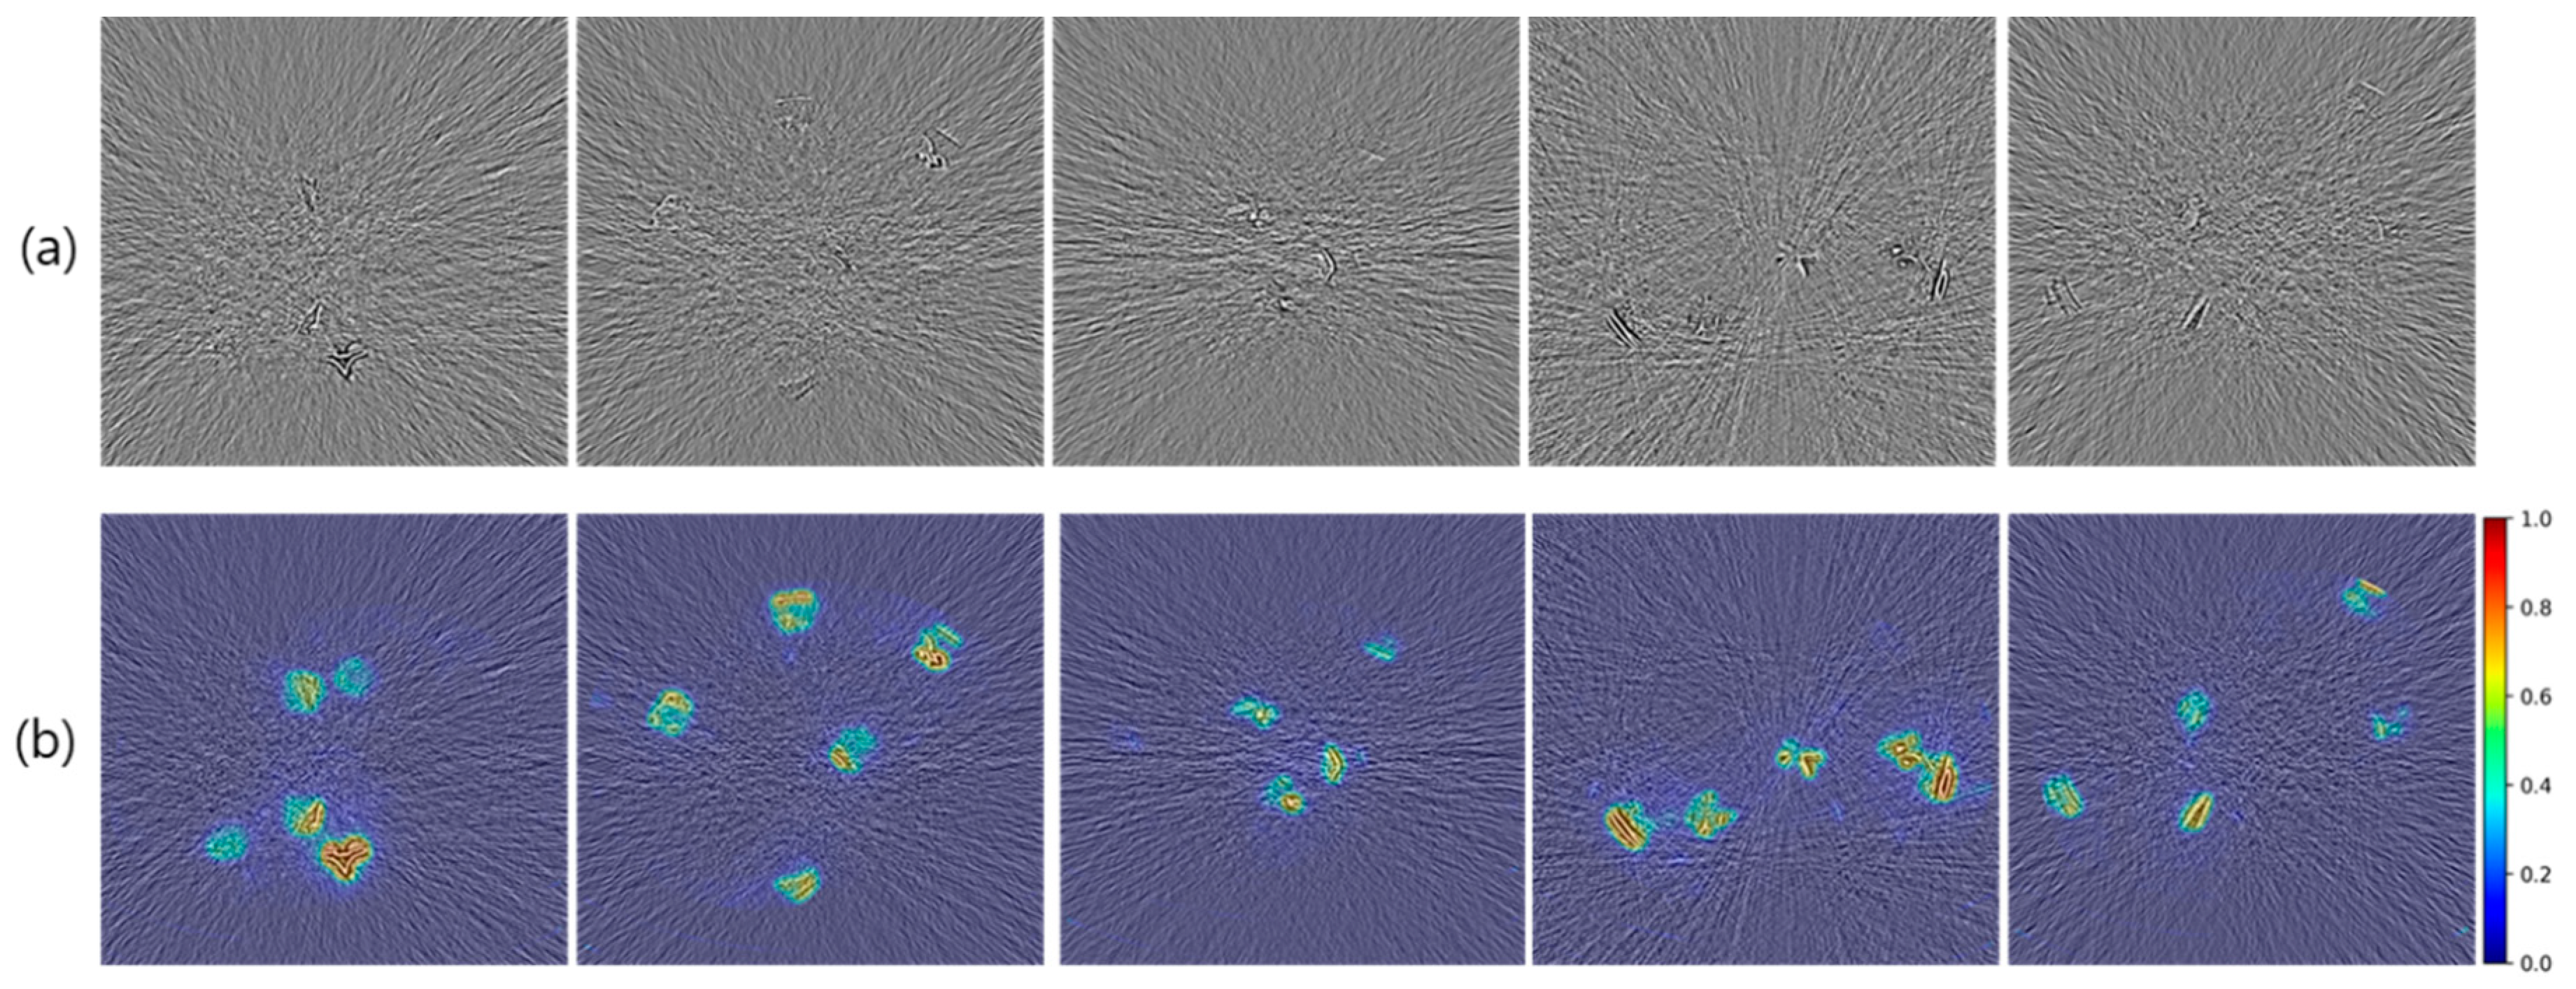

3.2. Verification of Prediction Performance with Heatmap

3.3. Verification of Prediction Performance with RSI Measurements